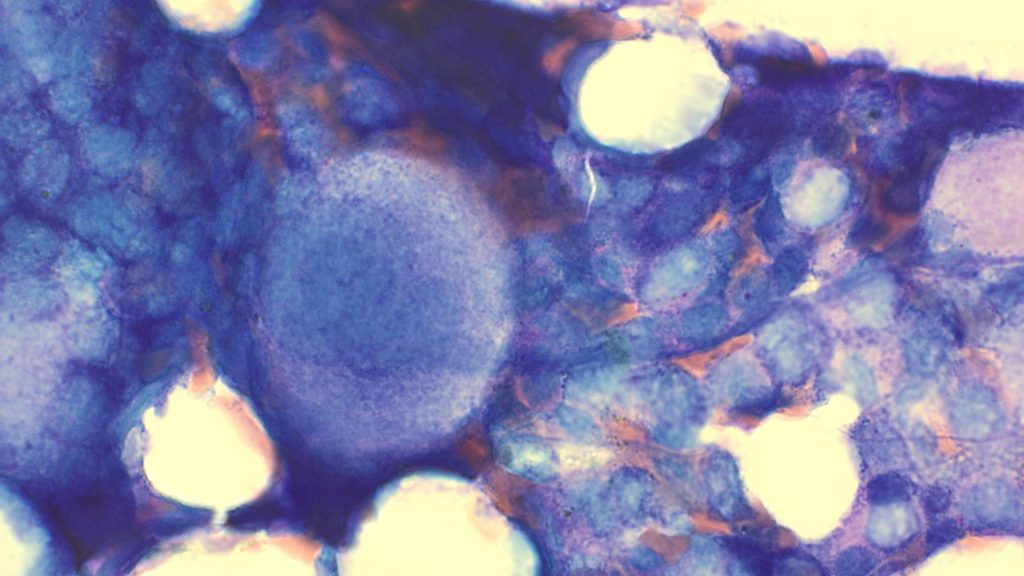

Megakaryocytes

Abnormal cytoplasm

Micromegakaryocytes

Separated nuclei

Hypolobated nuclei